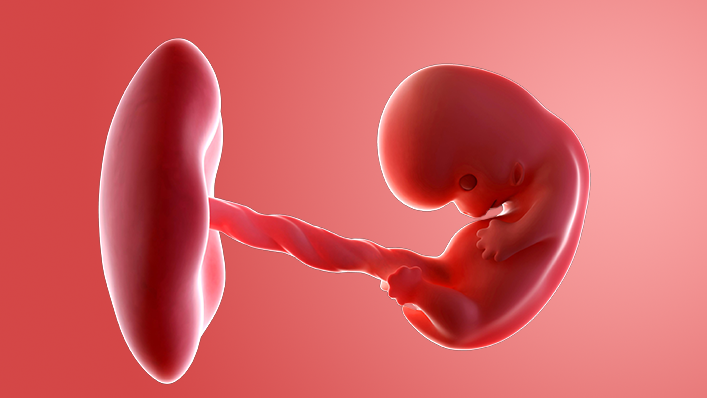

What does my baby look like?

Your baby, or foetus, is now around 22mm long from head to bottom, which is about the size of a strawberry.

The face is looking more recognisable, with eyes protected by eyelids, a little mouth and even a tongue with tiny taste buds.

The hands and feet are developing, but there are no fingers or toes yet, just grooves where they will be.

All the major internal organs – the heart, brain, lung, kidneys and gut – are developing. Bones are starting to form.

Your baby's genitals are also starting to take shape – but you probably won't find out if it's a boy or a girl until your anomaly scan at around 18 to 21 weeks.